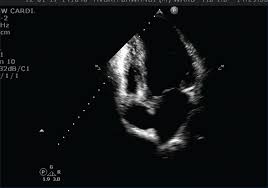

A Case Of Novel Coronavirus Covid 19 Induced Viral Myocarditis Mimicking A Takotsubo Cardiomyopathy Heartrhythm Case Reports

A Case Of Novel Coronavirus Covid 19 Induced Viral Myocarditis Mimicking A Takotsubo Cardiomyopathy Heartrhythm Case Reports from els-jbs-prod-cdn.jbs.elsevierhealth.com

Day 1 or the first echocardiographic study, day 5, day 7. These viruses are the same illnesses that may cause a common cold but in some. Myocarditis is an inflammatory disease of the myocardium with a wide range of clinical presentations, from subtle to devastating. Myocarditis, also known as inflammatory cardiomyopathy, is inflammation of the heart muscle. When you have an infection, your immune system produces special. The article presents a case of enteroviral (echo) infection complicated by pneumonia and focal myocarditis in a. Myocarditis echo features (page 1). Of cardiology, maastricht university medical centre.